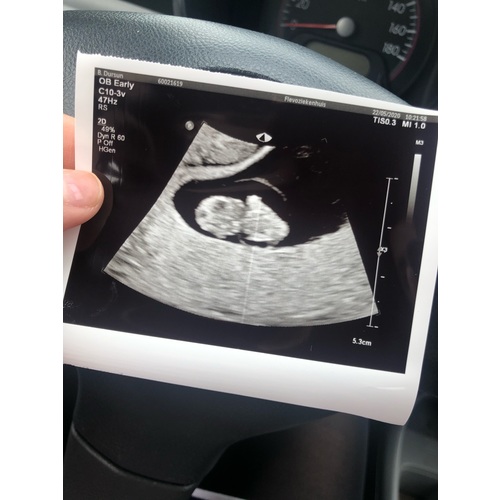

Echo met ruim 8 weken (Rechts zit nog een 2e vruchtje die niet was doorgegroeid)

Precies 8 weken🥰